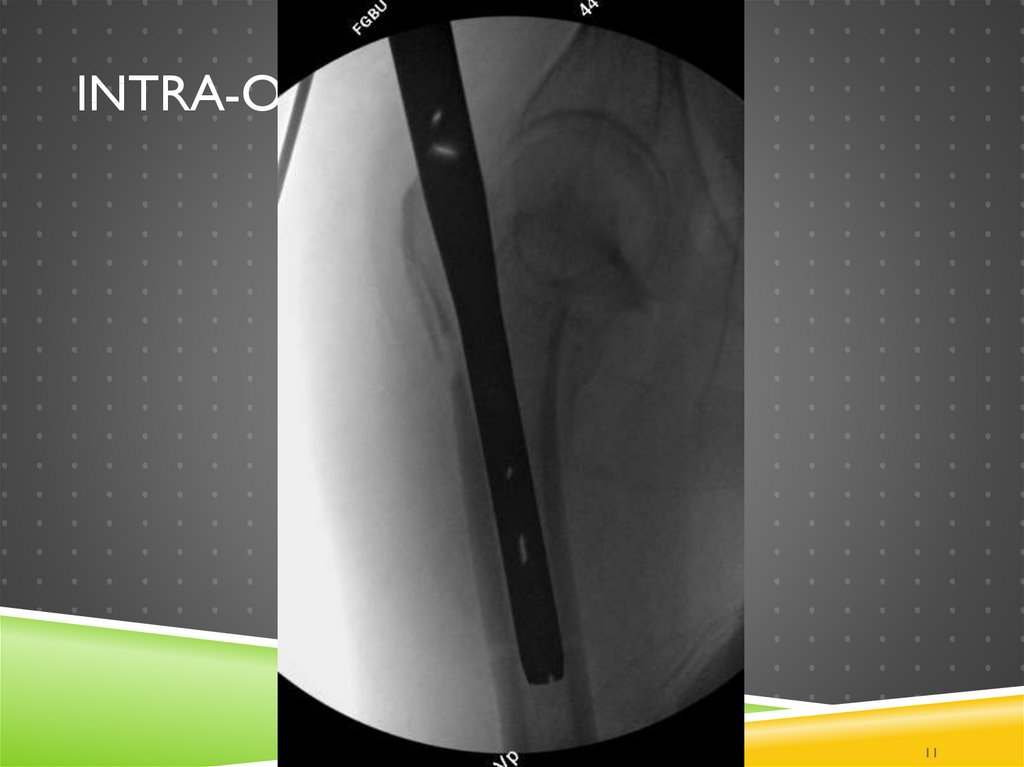

9. Intra-op

INTRA-OP

1

9